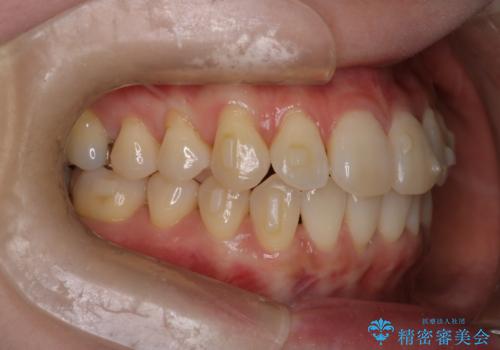

【インビザライン】かみ合わせを整えたい

- インビザラインで非抜歯治療を行いました。IPRと拡大をし、叢生、咬合をきれいにしました。

主訴であったかみ合わせを正しい位置に動かし、バランスよくかめるようになりました。矯正治療終了後にメタルインレーをセラミックインレーに替えました。